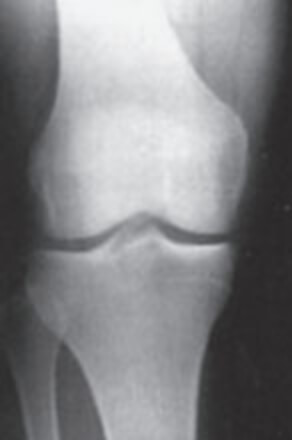

0 正常な膝のレントゲン画像

K-L分類Grade0のX線画像